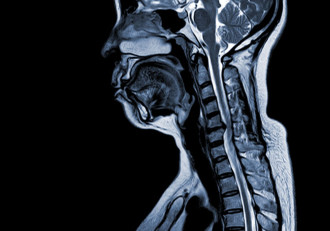

Magnetic resonance imaging plays a pivotal role in the diagnosis, staging and follow-up of head and neck cancers, a diverse group of malignancie1